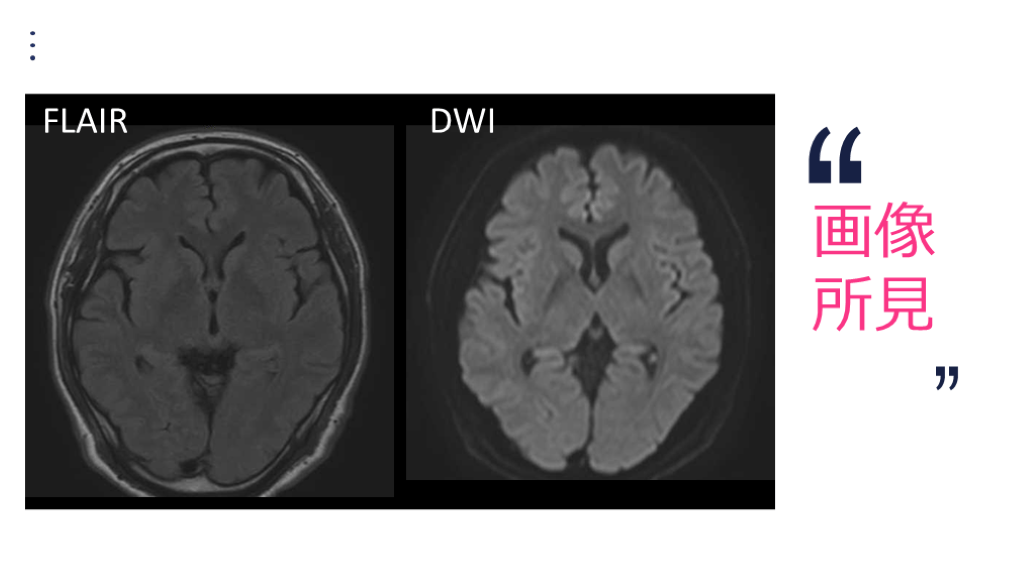

画像 所見

画像 所見 FLAIR DWI